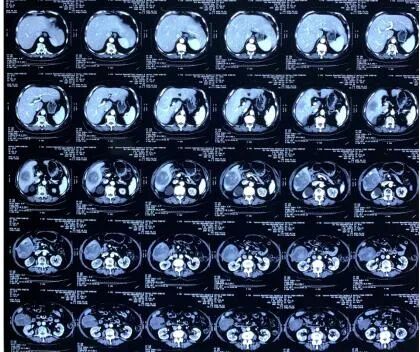

下一步治疗该如何选择,是手术切除还是保守治疗?杨云表示,从影像学资料来看,肿瘤尚未出现远处转移迹象,适合手术,无奈老人年纪大了,加之有糖尿病等慢性病,手术风险及术后出现并发症的风险均较高。如果选择保守治疗,介入、放疗等治疗手段也多,但疗效相对差一些。面对一名86岁的老人,一个两难的选择摆在医生与家属面前。

麻醉前,范奶奶向杨云竖了竖大拇指。医患对视,信任在眼神中传递。打开腹腔后,杨云一眼便看到肝脏VI段肿瘤突出于肝脏表面,周围环绕着大量已经凝固的黑色血凝块。由于此前肿瘤破裂,部分大网膜、结肠、十二指肠覆盖到肿瘤破溃处,这一人体精妙的自我保护机制,如今给手术团队制造了极大的难题。